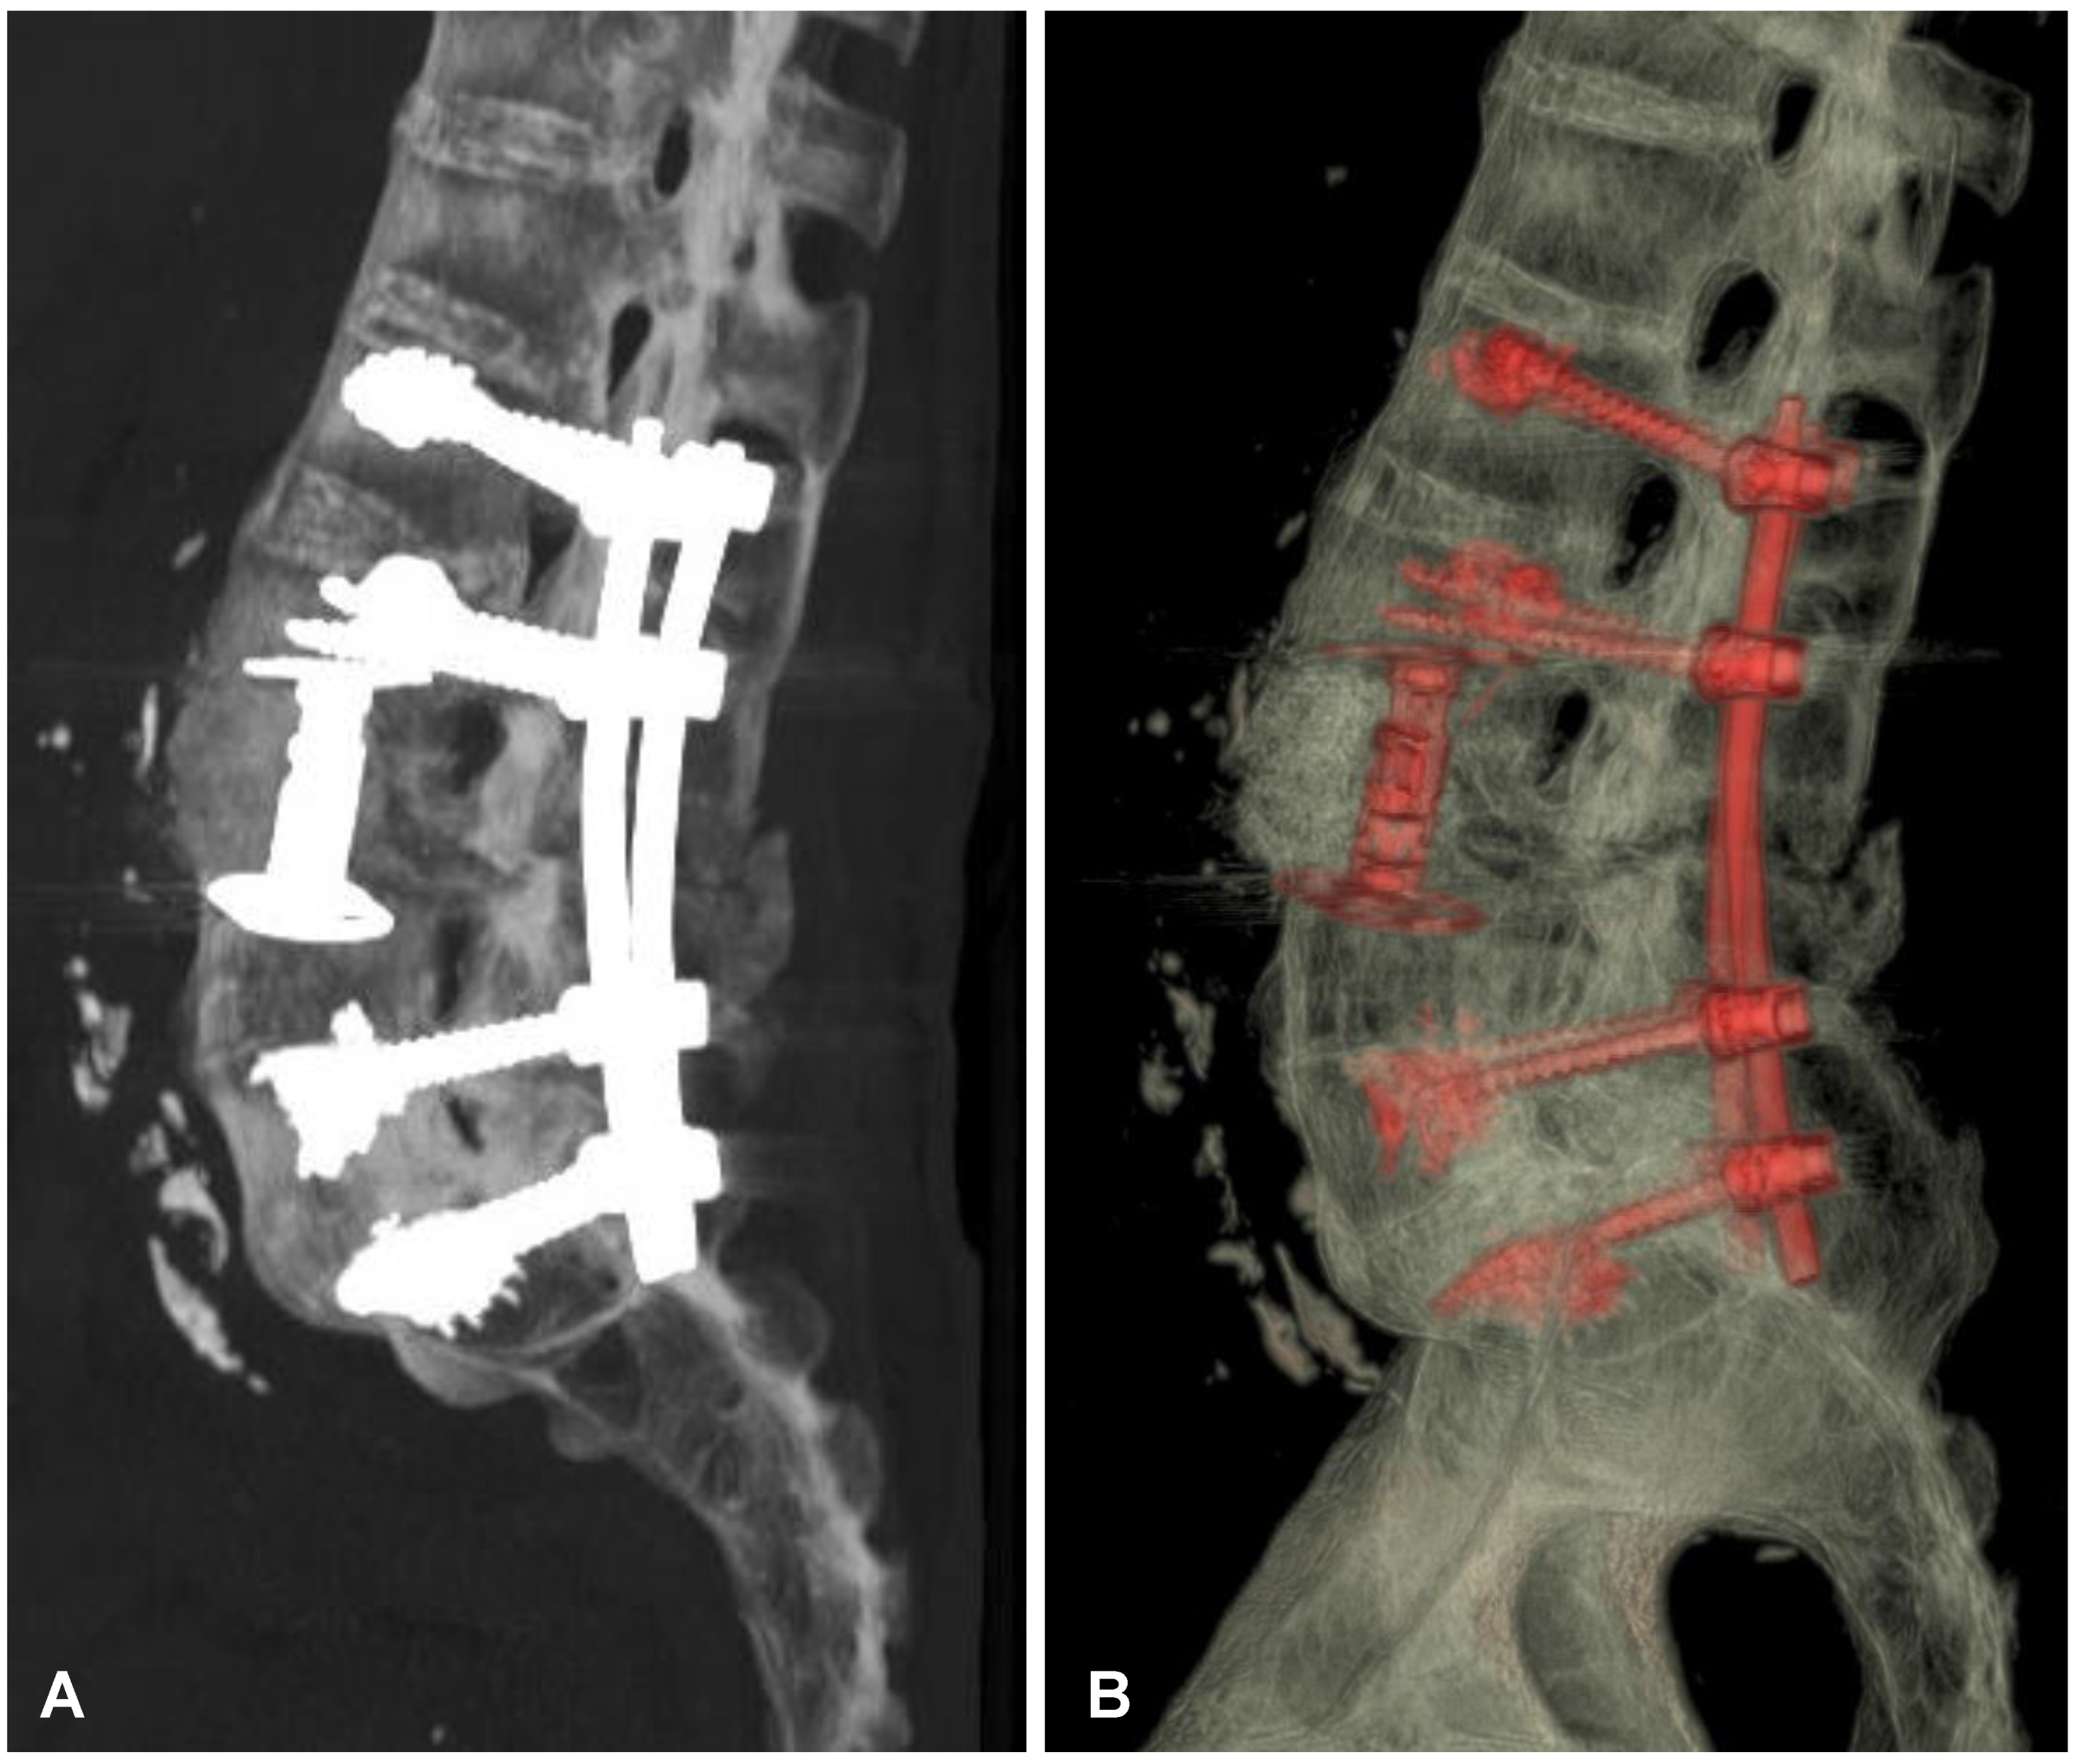

Figure 6. Postoperative CT-based reconstruction of the lumbar spine demonstrating correct positioning of the anterior and posterior spinal implants at the L2-L3-L5-S1 levels (A,B).

After initial diagnostics and preparations, the patient was transferred to the operating room. The posterior percutaneous transpedicular stabilization at the L2-L3-L5-S1 levels (Mantis; Stryker, Kalamazoo, MI, USA) with cement augmentation (VertaPlex HV; Stryker, Kalamazoo, MI, USA) for each inserted screw (4 mm × 6.5 mm/50 mm; 4 mm × 6.5 mm/45 mm) under intraoperative 2-dimensional (2-D) fluoroscopy control was performed in the first stage of surgery. In the second stage of surgery, from a lateral approach, the left side of the retroperitoneal cyst was emptied, and watery/light yellow fluid similar to urine was obtained. Therefore, a distractible vertebral body replacement implant (AsterX; Medtronic, Minneapolis, MN, USA) was placed between the L3 and L4 bodies with the placement of a retroperitoneal precutaneus Redon drainage system. A control CT scan performed one day after the operation revealed the correct placement of all the implants (Figure 5 and Figure 6). The second CE-CT scan performed two days after surgery consecutively showed evidence of post-traumatic right ureteral injury, urine leakage, and hydronephroureter (Figure 7). The general examination of intraoperatively obtained fluid revealed the following results: pH: 9.0; protein: 600 mg/dL; transparency and color before centrifugation: sanguine and cloudy; transparency and color before centrifugation: transparent and dark yellow; absolute leukocytes (LEU): 1197 cells/μL; and sediment: single round epithelium in the sample with erythrocytes loosely cover the field of vision (15–20 in the counterfield). The microbial culture of the intraoperative obtained fluid after 7 days was negative. After 4 days, the patient was transferred to another local hospital specializing in urological care. Due to the overall late presentation covering advanced hydronephrosis, ureteric stricture formation, and non-functional kidney, the nephrectomy and ureter ligation were performed. After urological treatment, the patient has been on follow-up for 2 years with no evidence of neurological or urological problems.